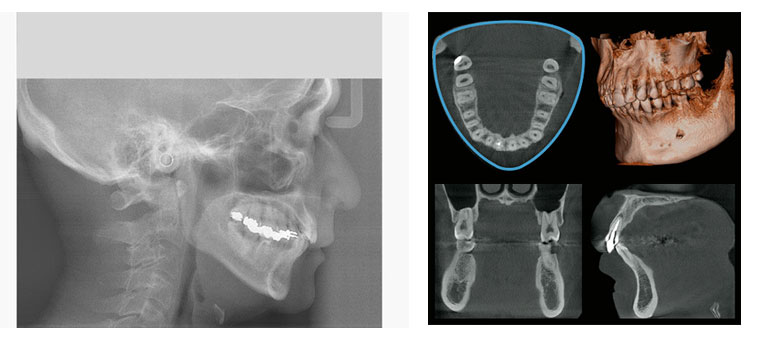

先進医療機器である歯科用CTレントゲンを導入しています。通常のデジタルレントゲンは白黒の2Dでのレントゲン撮影だけですが、歯科用CTレントゲンでは写真のような3Dでの撮影が可能です。

【使用用途】根幹治療・親知らず・歯周病治療・歯根の破折・歯列矯正・顎関節症・インプラント治療

撮影領域を選択できるため、患者様への放射線量を減らすことが可能です。CTレントゲンの利点は、骨の水分量や骨密度まで把握できる点にあります。若い患者様の場合、骨密度が高く、水分量も問題ないことが多いですが、高齢の患者様では骨密度や水分量が低い場合もあります。また、歯の下を通る神経の位置も個人差があります。

かつては歯科医師が経験や勘に頼って治療を行っていた時代もありましたが、CTレントゲンの導入により、根拠に基づいた治療が可能となりました。